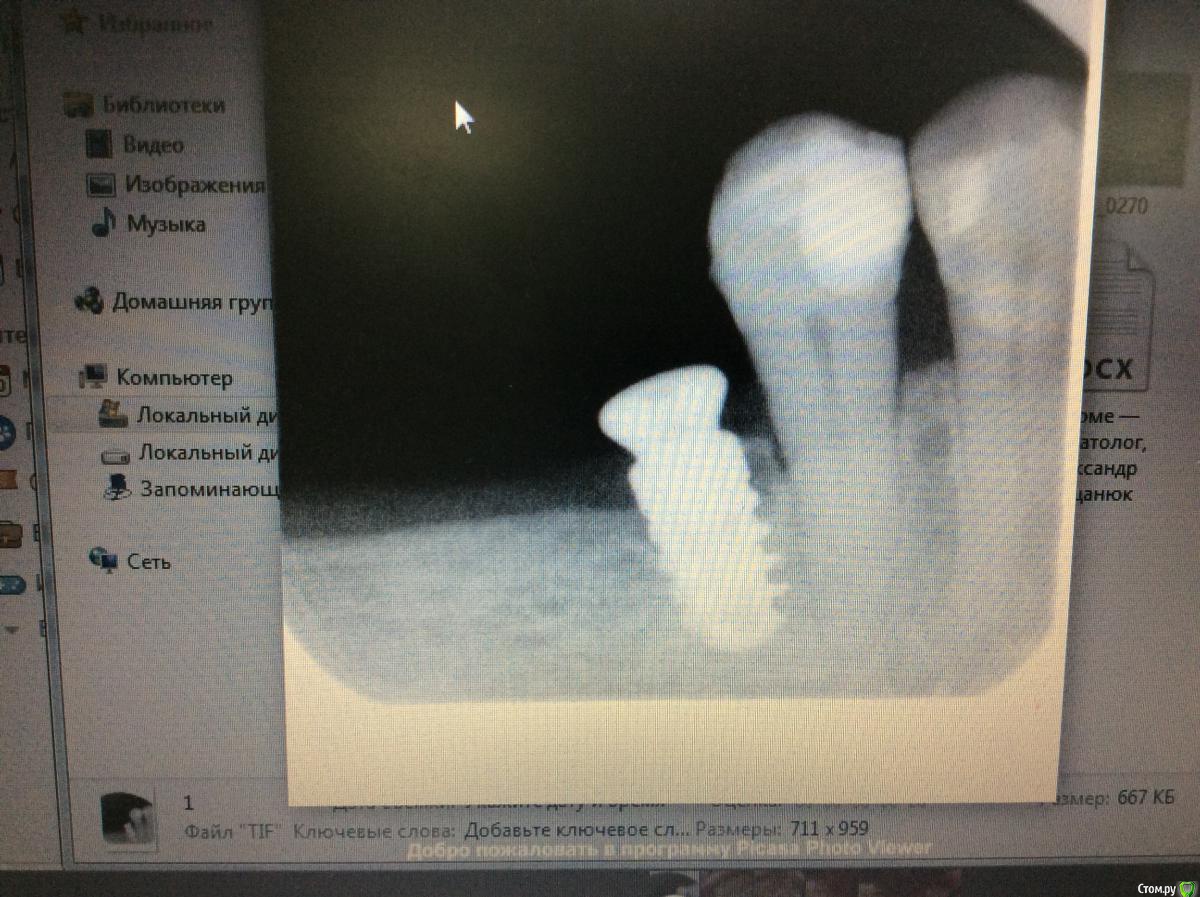

Nazim_NV86 Опубликовано 1 декабря, 2018 Поделиться Опубликовано 1 декабря, 2018 Поддерживаю.Убирайте имплантат.И не забудьте поставить его поглубже. Он в вашем случае должен стоять не апикальнее вестибулярной кости соседнего зуба. Ссылка на комментарий

Bier Опубликовано 5 декабря, 2018 Поделиться Опубликовано 5 декабря, 2018 мне думается, что вы выбрали слишком широкий диаметр и очень сильно недозаглубили имплантат. 3 Ссылка на комментарий

Pavel-Pskov Опубликовано 5 декабря, 2018 Поделиться Опубликовано 5 декабря, 2018 Диаметр походит на 3.8. Нет? Ссылка на комментарий